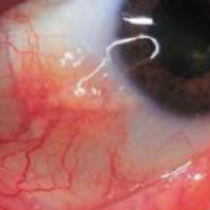

| Eye symptoms | |

| H15.00 | Scleritis |